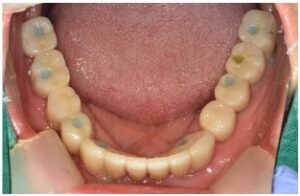

식립 후 2달이 지났을 때

아래턱 앞니와

왼쪽 어금니 부위에

심어둔 임플란트 주변으로

잇몸뼈가 잘 회복하고 있는 것을

확인하였으며

먼저 위턱 어금니와

아래턱 오른쪽 어금니의

지대주 제작을 위한

coping 인상채득을 진행하였는데요.

Fixture와 보철물을 연결해 주는 지대주를

개인의 구강 상황에 맞는

맞춤형 지대주를 이용하였으며

기공소에서 만들어온 임시 치아를 통해

최종 보철물을 제작하기 전

무너진 교합과 수직 고경을 회복시키고,

구강 근육 및 점막 안정화를 위한

시간을 가지기로 하였습니다.